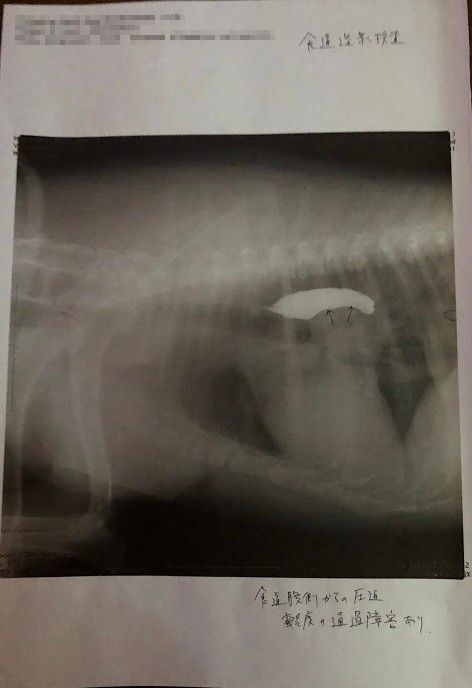

↑バリウム飲んで検査してもらった所、矢印の部分に腫瘍があり(白い部分は食道)、それが食道を押し上げているため、飲んだ水を吐いたりするとの事でした。(この時点で5センチほどの大きさの腫瘍)

↑腫瘍の場所が体の奥のにある為、CT検査できる大学病院で検査してから手術するかどうか決めたほうがいいと言われました。

手術するとしても場所的にかなり難しいものになると思うので、年齢を考えて手術するかどうかよく考えたほうがいいと。。。

ただ、今後腫瘍がさらに大きくなるかもで、その場合、固形のものは食べられなくなり流動食になるかもしれないとも言われました。